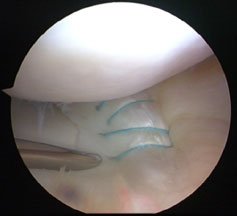

A meniscal tear is a relatively important diagnosis to make, and more importantly it is a relatively important problem to sort out acutely (a) because it is really painful and (b) because the best time to fix the meniscus is in that early period just after the knee has been injured (within six weeks). If someone comes in with a locked knee though, you don’t leave them stewing for six weeks - they should be admitted straight away. You can get an MRI – there is no harm in getting additional information – but the knee needs to be unlocked and generally speaking that means an arthroscopy, the flipped meniscus is reduced and it is stitched back into postion if you have the skills to do that. We routinely now carry out meniscal repair in that sort of situation.